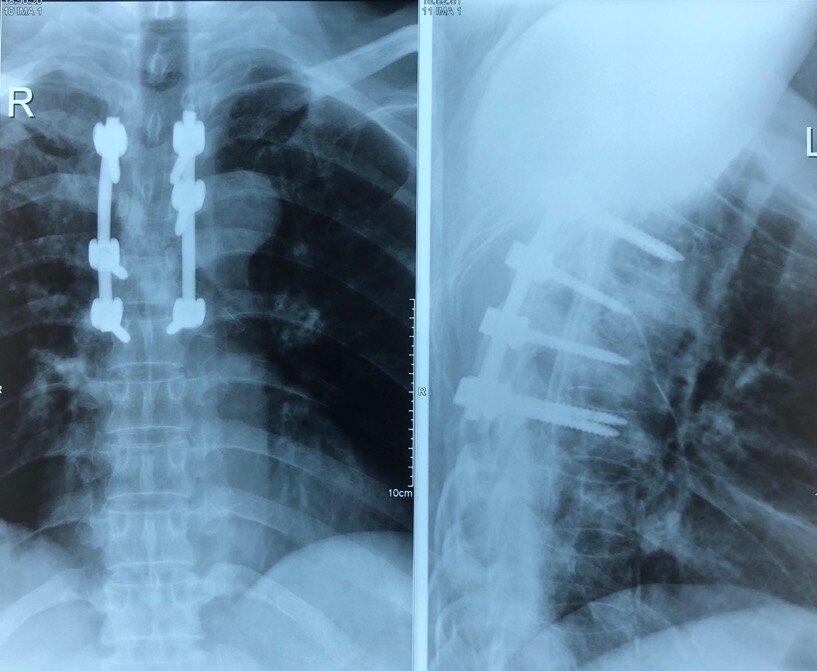

该患者在进行规范化抗结核治疗两个月,以后病情得到相对稳定,结核得到相对控制,但脊柱破坏引起的疼痛持续存在。后进行手术治疗。?手术在全麻下进行,行胸椎结核病灶清除+局部抗结核药物应用+植骨融合内固定术。

患者的胸椎结核病灶得到清除,胸椎破坏以后形成的椎间不稳定得到加固,患者疼痛明显缓解,并且避免了脊柱稳定性破坏引起的脊柱侧弯和后突畸形,后续继续进行抗结核治疗,能够得到完全治愈。